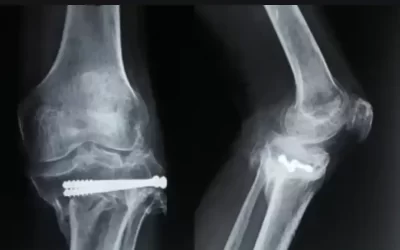

KNEE REPLACEMENT

Knee Replacement Surgery is usually performed in Severe-stage arthritis and very rarely for the other conditions.

Total Knee Replacement (TKR) Using Stryker Triathlon System

Dr Chethan has performed successfully Total Knee Replacement using Stryker Triathlon System A...